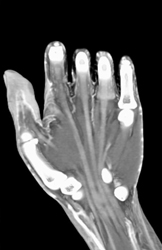

CTA of the Hand